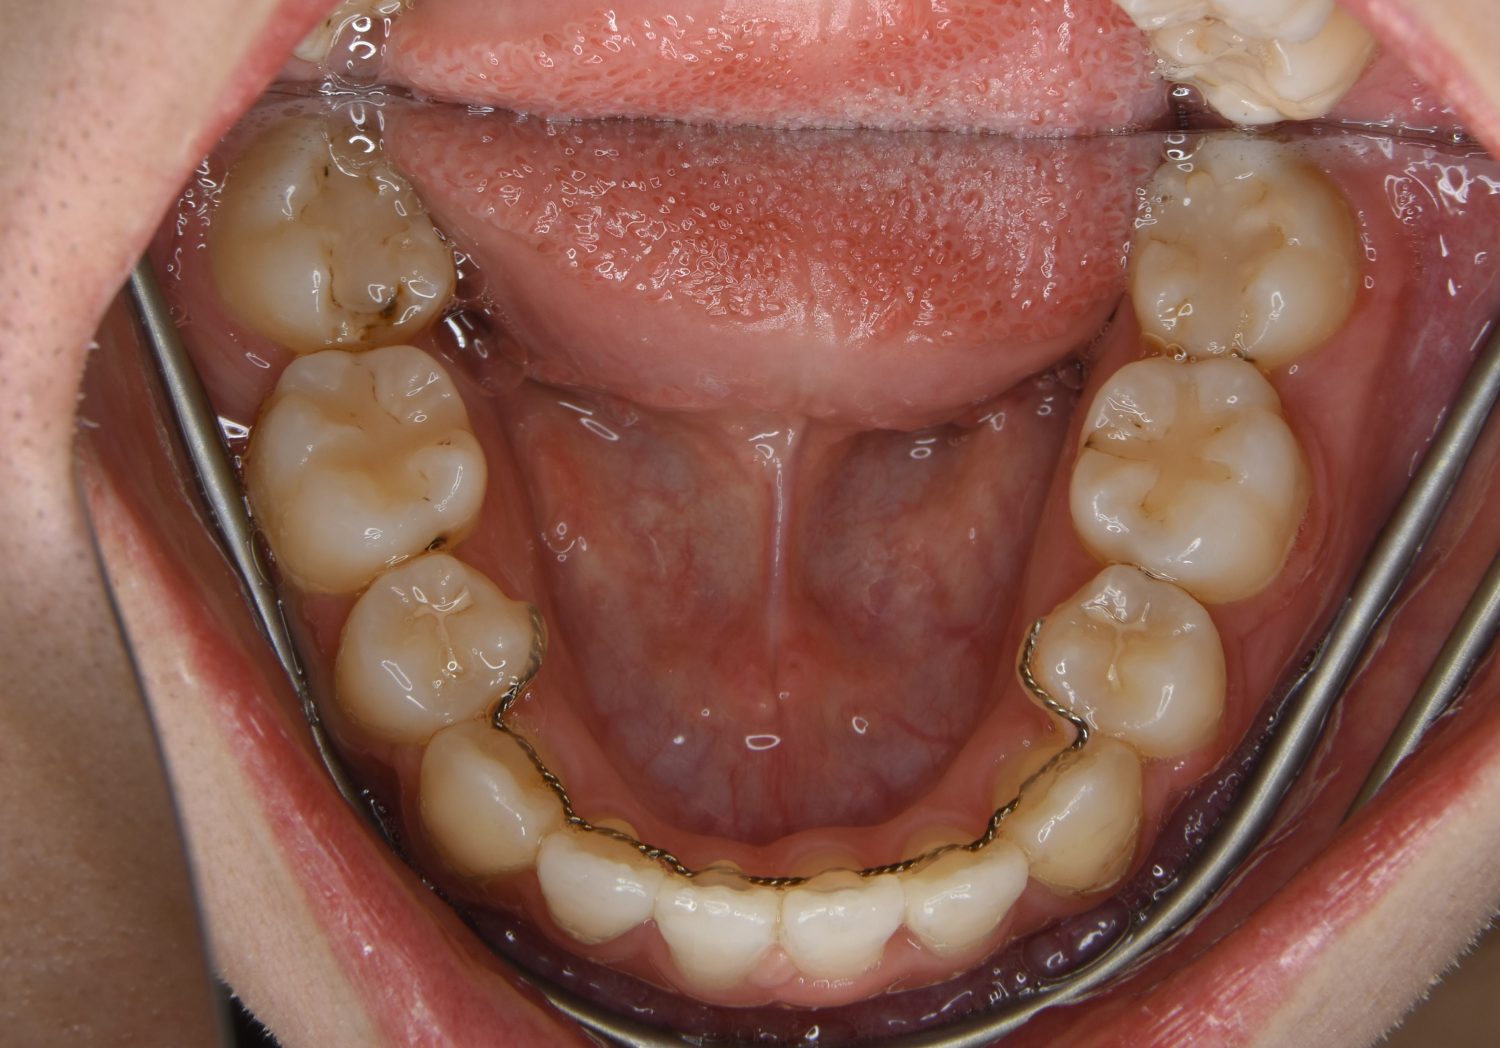

前歯部開咬の症例紹介②

Before

主訴

前歯で物が噛めない

治療内容

上下ラビアルブラケット(唇側装置)に矯正用アンカースクリューを併用し非抜歯で治療を行いました。

治療費

1,000,000 円(税込)

治療期間

26ヶ月

通院回数

27回

想定されたリスク

※歯根吸収、歯肉退縮、歯髄壊死、顎関節症状

上下の前歯が開いており前歯では全く噛めていない状態でした。臼歯の圧下を行うことで機能面のみでなく審美面も改善しました。